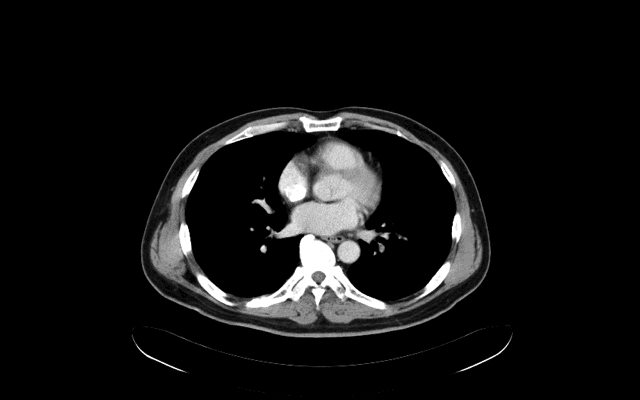

2010年的個案,66歲肺癌患者,

右上肢腫痛約3天,右側鎖骨下靜脈有人工血管(port-A)